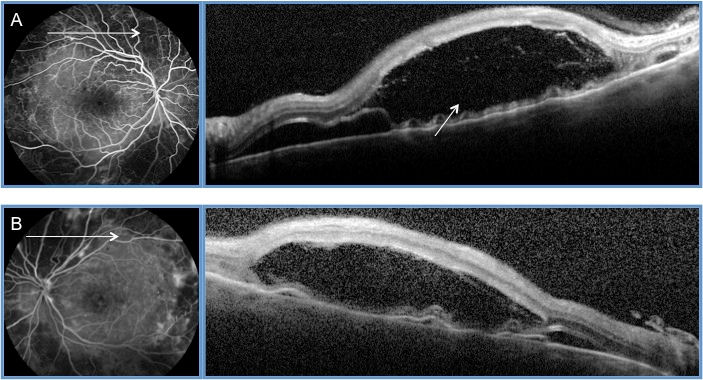

Fundus examination showed extensive pan-retinal laser burns with large perimacular serous retinal detachment at the level of the temporal superior arcade as confirmed on SD-OCT (Figure 2 [Fig. 2]). FFA revealed a marked reversal of microvascular lesions and leakage. During the following days, her vision further dropped to Count Fingers (CF) due to worsening of her retinal detachment. 2 sub-conjunctival injections of 0.1 ml Betamethasone were done 24 hours apart on each eye. One month later, her BCVA improved to 20/30. SD-OCT confirmed regression of retinal detachment.

Figure 2: SD-OCT showing a large serous retinal detachment (SRD) at the level of the temporal superior arcade (arrow) OD 2 days following PRP with the PASCAL photocoagulator (A). A similar image was seen in the fellow eye (B).